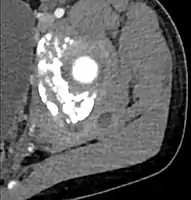

CT exam showing a multiloculated fluid collection in the left gluteus minimus muscle found to be a staph aureus pyomyositis in a 12-year-old healthy boy.

Axial T1 weighted fat suppressed post IV gadolinium contrast enhanced MRI image showing a mutliloculated bacterial abscess in the left gluteal muscle which grew Staphylococcus aureus (methicillin sensitive) thought to be due to tropical pyomyositis.

Coronal fat suppressed post contrast image showing a multiloculated bacterial abscess in the left gluteus minimus muscle due to tropical pyomyositis.

Coronal T2 weighted fat suppressed image showing a multiloculated fluid collection in the left gluteal musculature due to tropical pyomositis in a 12-year-old boy.